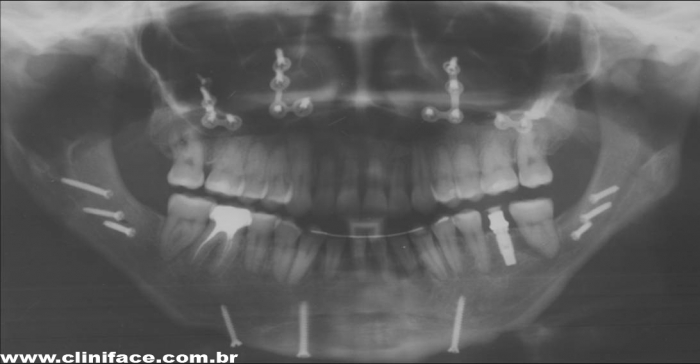

Raio x panorâmico final